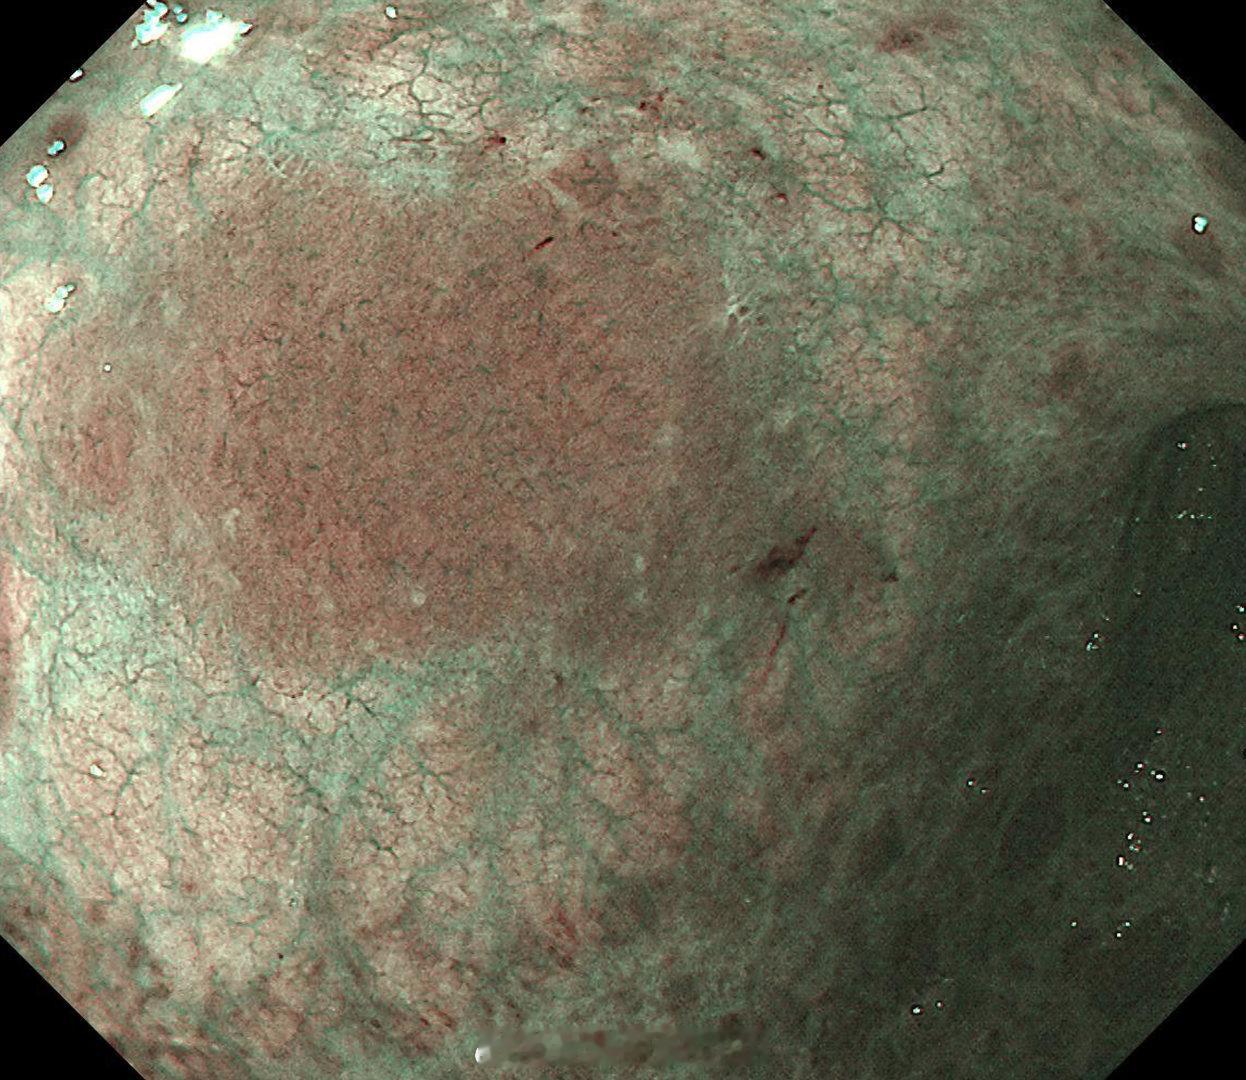

这是个常州来找我会诊的疑难杂症,当地觉得萎缩一塌糊涂,但是活检也没有提示啥病因,一开始我接诊也觉得是自身免疫性胃炎,但是抽血指标都不符合,最后在几块残余正常黏膜表现中看到了点蛛丝马迹,活检加上masson染色确诊是胶原性胃炎,以前不认识的时候这个世界都没这个病,一旦会诊断以后,满眼都是这类病[允悲][允悲][允悲]

这是个常州来找我会诊的疑难杂症,当地觉得萎缩一塌糊涂,但是活检也没有提示啥病因,一开始我接诊也觉得是自身免疫性胃炎,但是抽血指标都不符合,最后在几块残余正常黏膜表现中看到了点蛛丝马迹,活检加上masson染色确诊是胶原性胃炎,以前不认识的时候这个世界都没这个病,一旦会诊断以后,满眼都是这类病[允悲][允悲][允悲]